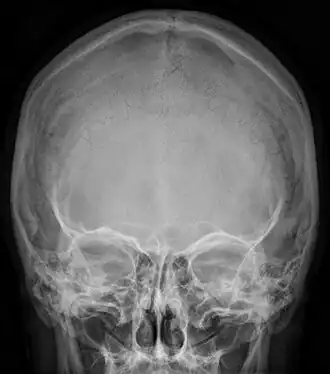

![]() Radiograph of the skull showing an interparietal bone between the occiput and parietal bones | |

An interparietal bone (os interparietale or Inca bone or os inca var.[1]) is a dermal bone situated between the parietal and supraoccipital. It is homologous to the postparietal bones of other animals.

In humans, it corresponds to the upper portion of the squama of the occipital bone that lies superior to the highest nuchal line and is completely fused to the supraoccipital. However, in some individuals this portion remains separate from the rest of the occipital bone throughout life. In such cases, this separate bone is particularly referred as Inca bone. Inca bones in humans were first found in the skulls of contemporary indigenous peoples of the southern Andes as well as in those of mummies of the Inca civilization. Although the Inca bone was originally encountered as a variation in South American and Latin American cranial remains, the variation occurs in people from all geographic regions of the world and is by no means indicative of South/Latin American origin.